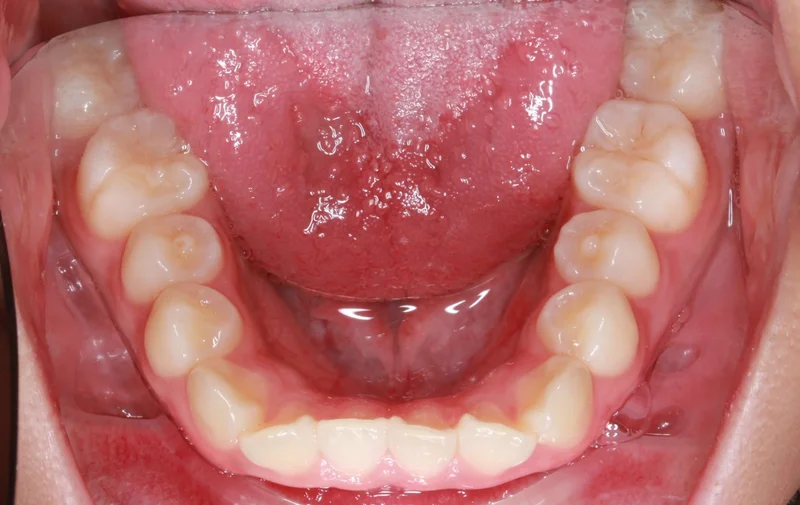

Lower

Lower - After Treatment

After